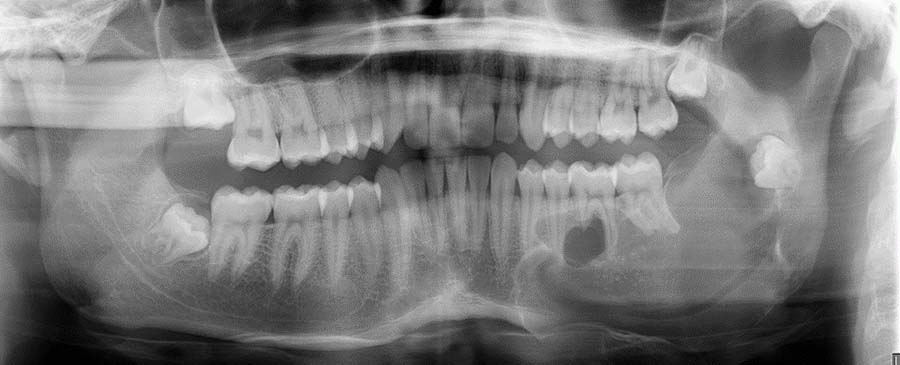

Oral & Maxillofacial Surgery

Our dedicated team of Oral and Maxillofacial Surgery specialists are committed to addressing a wide range of conditions affecting the mouth, jaw, and face, from complex traumatic injuries and cancer to reconstructive procedures.